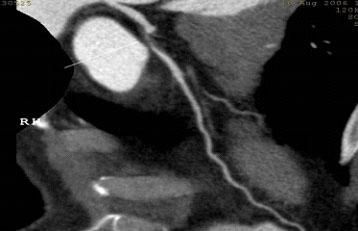

CT冠脈血管成像:

1.冠脈軟斑塊:

2.混合性斑塊:

3.對于斑塊性質的确定,CT優于DSA: